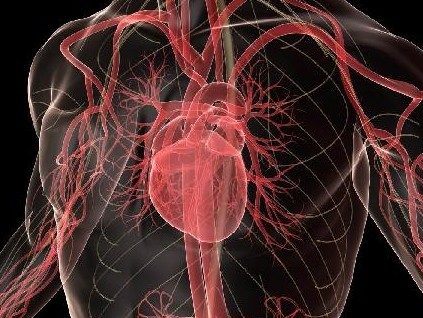

Η καρδιά προστατεύεται κατά των λοιμώξεων με πολλούς μηχανισμούς, ο κυριότερος όμως είναι η ανατομική της κατασκευή. Εσωτερικά καλύπτεται από έναν προστατευτικό χιτώνα που λέγεται ενδοκάρδιο, ο οποίος δεν επιτρέπει να εγκατασταθούν πάνω σε διάφορες περιοχές της καρδιάς μικρόβια τα οποία κυκλοφορούν στο αίμα.

Ομως όταν υπάρχει είτε βλάβη είτε τραυματισμός των βαλβίδων από διάφορα αίτια (π.χ. ρευματική αλλοίωση ή τραυματισμός του μυοκαρδίου από ηλεκτρόδια), τότε δημιουργούνται συνθήκες εγκατάστασης των μικροβίων. Τοπικά δημιουργείται μια μάζα από μικρόβια και στοιχεία του αίματος που λέγεται εκβλάστηση.

Οι εκβλαστήσεις αυξάνονται προοδευτικά σε μέγεθος και – πέραν της καταστροφής που προκαλούν τοπικά – τελικά προκαλούν είτε διάτρηση και ανεπάρκεια των βαλβίδων είτε περιφερικές εμβολές.

Τα έμβολα, δηλαδή τμήματα των εκβλαστήσεων, αποσπώνται και διά της κυκλοφορίας του αίματος μπορούν να σφηνωθούν σε διάφορες αρτηρίες, να διακόψουν τελικώς την κυκλοφορία του αίματος και να προκαλέσουν εγκεφαλικά επεισόδια, εμφράγματα του μυοκαρδίου ή εμβολές σε όλα τα ζωτικά όργανα του σώματος.